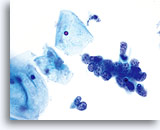

Overall cell size is usually larger than the normal counterpart. 60x

Nuclei “round up” compared to the normal nucleus. 60x

Nucleoli are common and vary in frequency, size and number. 60x

Endometrial adenocarcinoma 60x